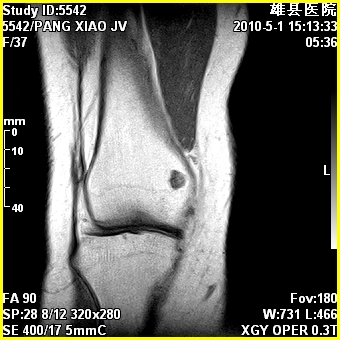

标题: MRI2894:患者右膝关节疼痛两月余,无明显外伤史 [打印本页]

标题: MRI2894:患者右膝关节疼痛两月余,无明显外伤史

右股骨下端前内侧类圆形异常信号,位于干骺端,呈长t1长t2改变,但信号不均,t1图上病灶中心见小片状稍高信号影,t2图上见散在稍低信号影,stir像呈高信号,因病灶较小,缺乏特征性改变,结合患者年龄及部位,考虑嗜酸性肉芽肿可能性大。胫骨关节面下的小囊状异常信号,如果一元论考虑则为嗜酸性肉芽肿,不过发生在这个部位的少见,二元论考虑为邻关节骨囊肿。半月板与前后交叉韧带均未见异常。

右股骨下端前内侧干骺端囊性良性病变,考虑 1内生软骨瘤 2骨囊肿 3肉芽肿。

考虑---骨囊肿或肉芽肿可能性大。

内生软骨瘤

临关节骨囊肿可优先考虑